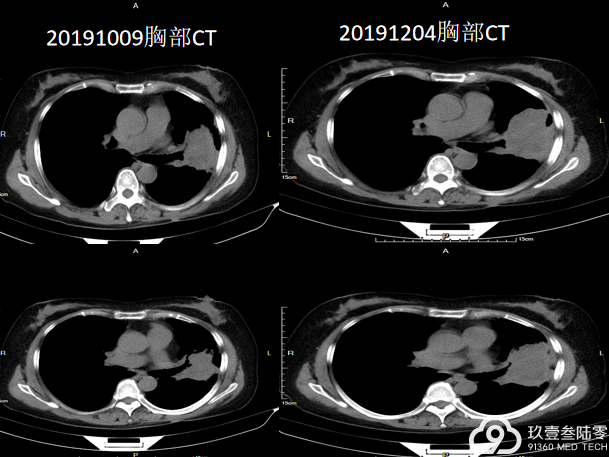

2018-11-22来我院行胸腹部CT示:

1、左侧胸腔占位,考虑恶性,胸膜间皮瘤侵及左肺及左主支气管可能性大,建议结合病理。

2、右肺下叶炎症。

3、左侧胸腔大量积液。

4、腹部CT未见异常

双侧胸廓不对称,纵隔右侧移位,左侧胸腔一巨大团块状高密度影,大小约13.8cm×9.4cm×16.6cm(前后径×左右径×上下径),余肺组织呈受压改变,左侧胸膜呈结节样增厚,增强后呈轻度不均匀强化,内见相对低密度区。左主支气管内见结节样软组织密度影,呈轻度强化,余气管、支气管通畅,纵隔内未见明显肿大淋巴结,左侧胸膜腔见明显积液征象。